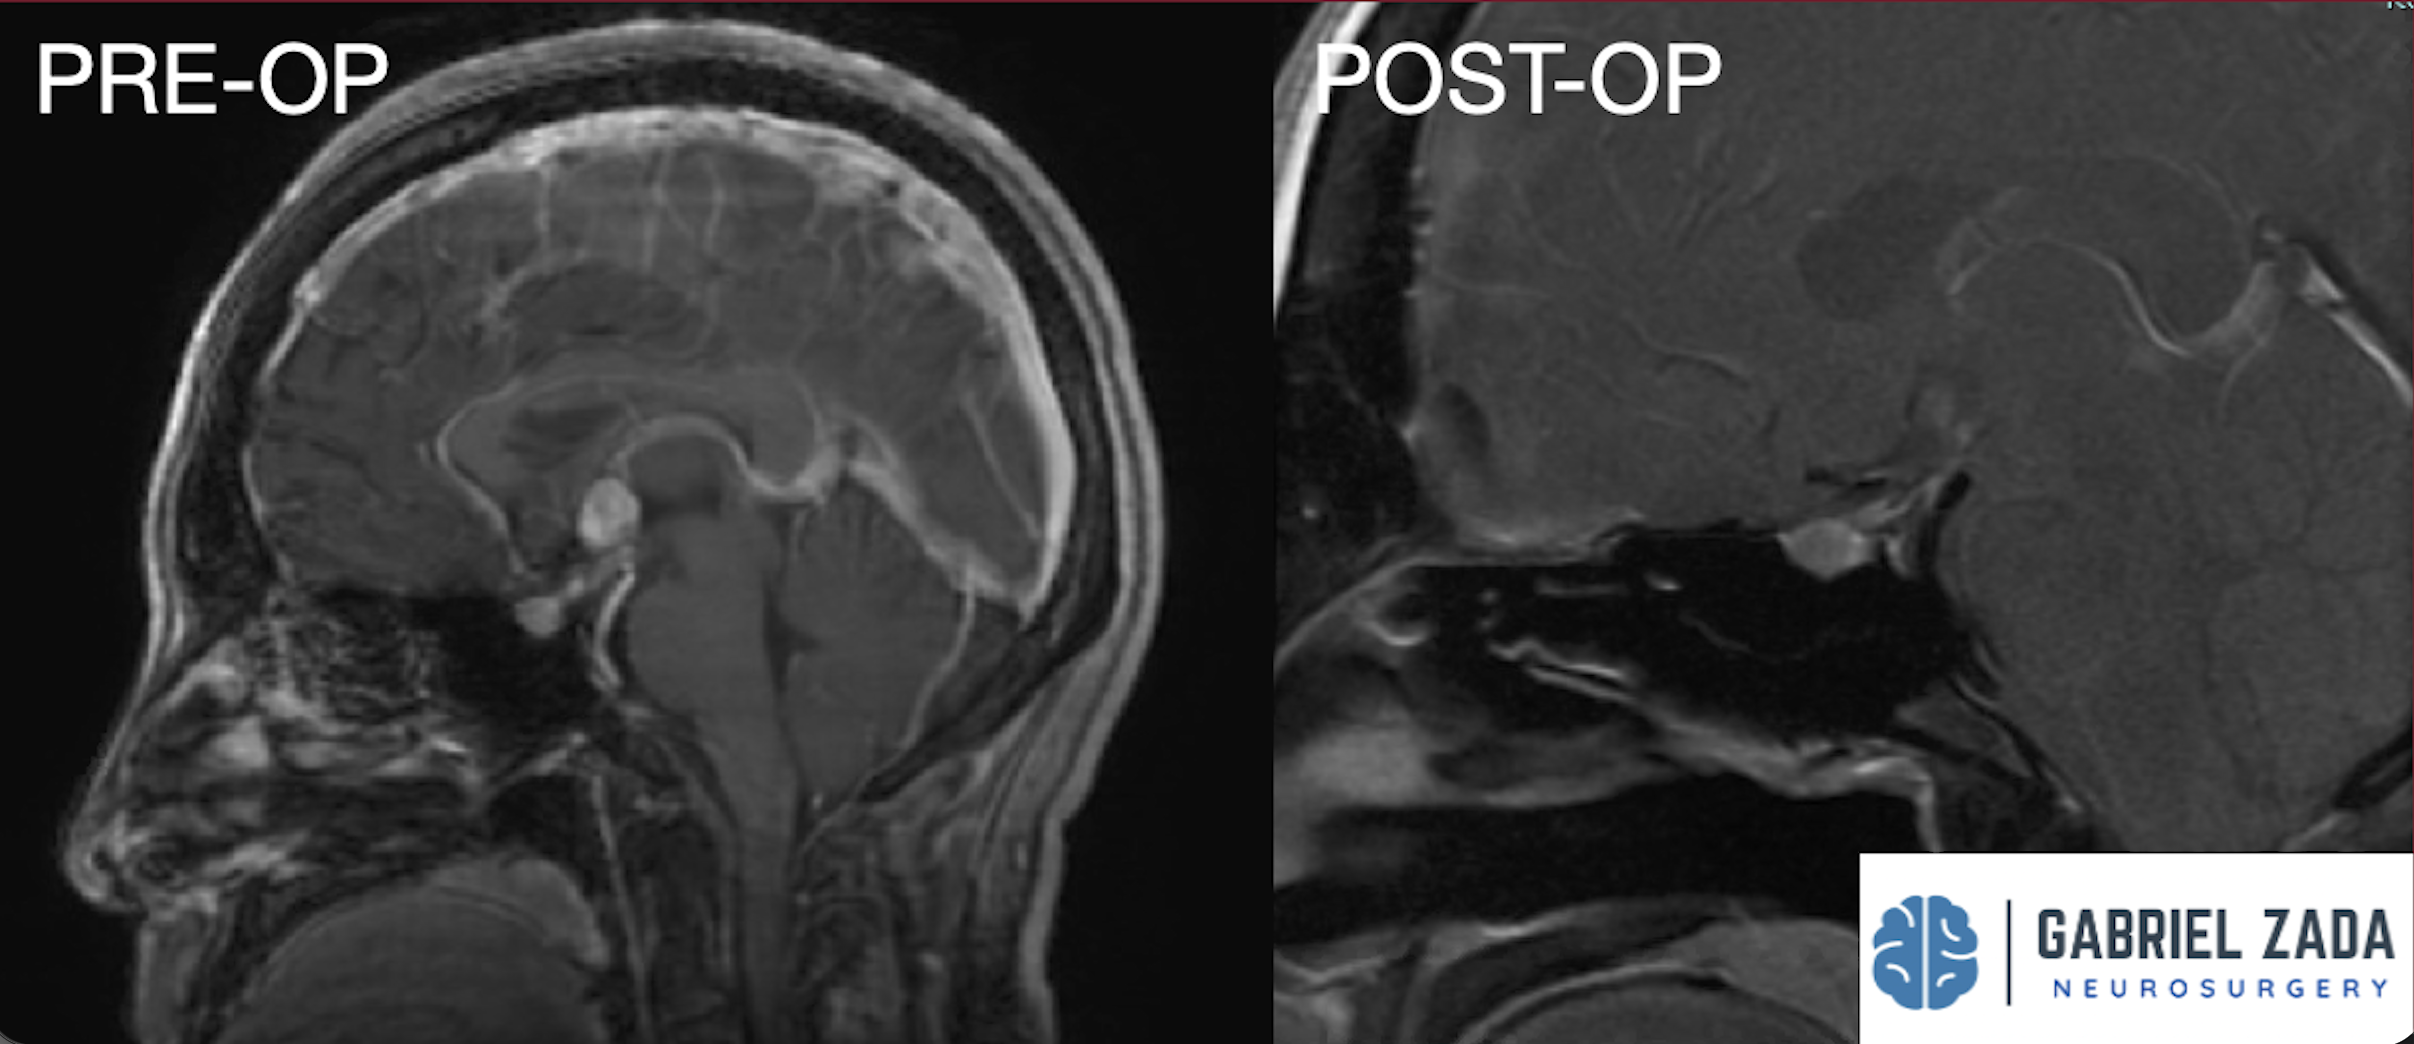

Explore this comprehensive gallery featuring pre‑ and post‑operative imaging of patients with skull‑base tumors treated by Gabriel Zada, MD, MS, FAANS, FACS. These cases highlight Dr. Zada’s expertise in advanced neurosurgical techniques and outcomes.

*Representative cases shown for educational purposes. All images de-identified. Individual results vary.